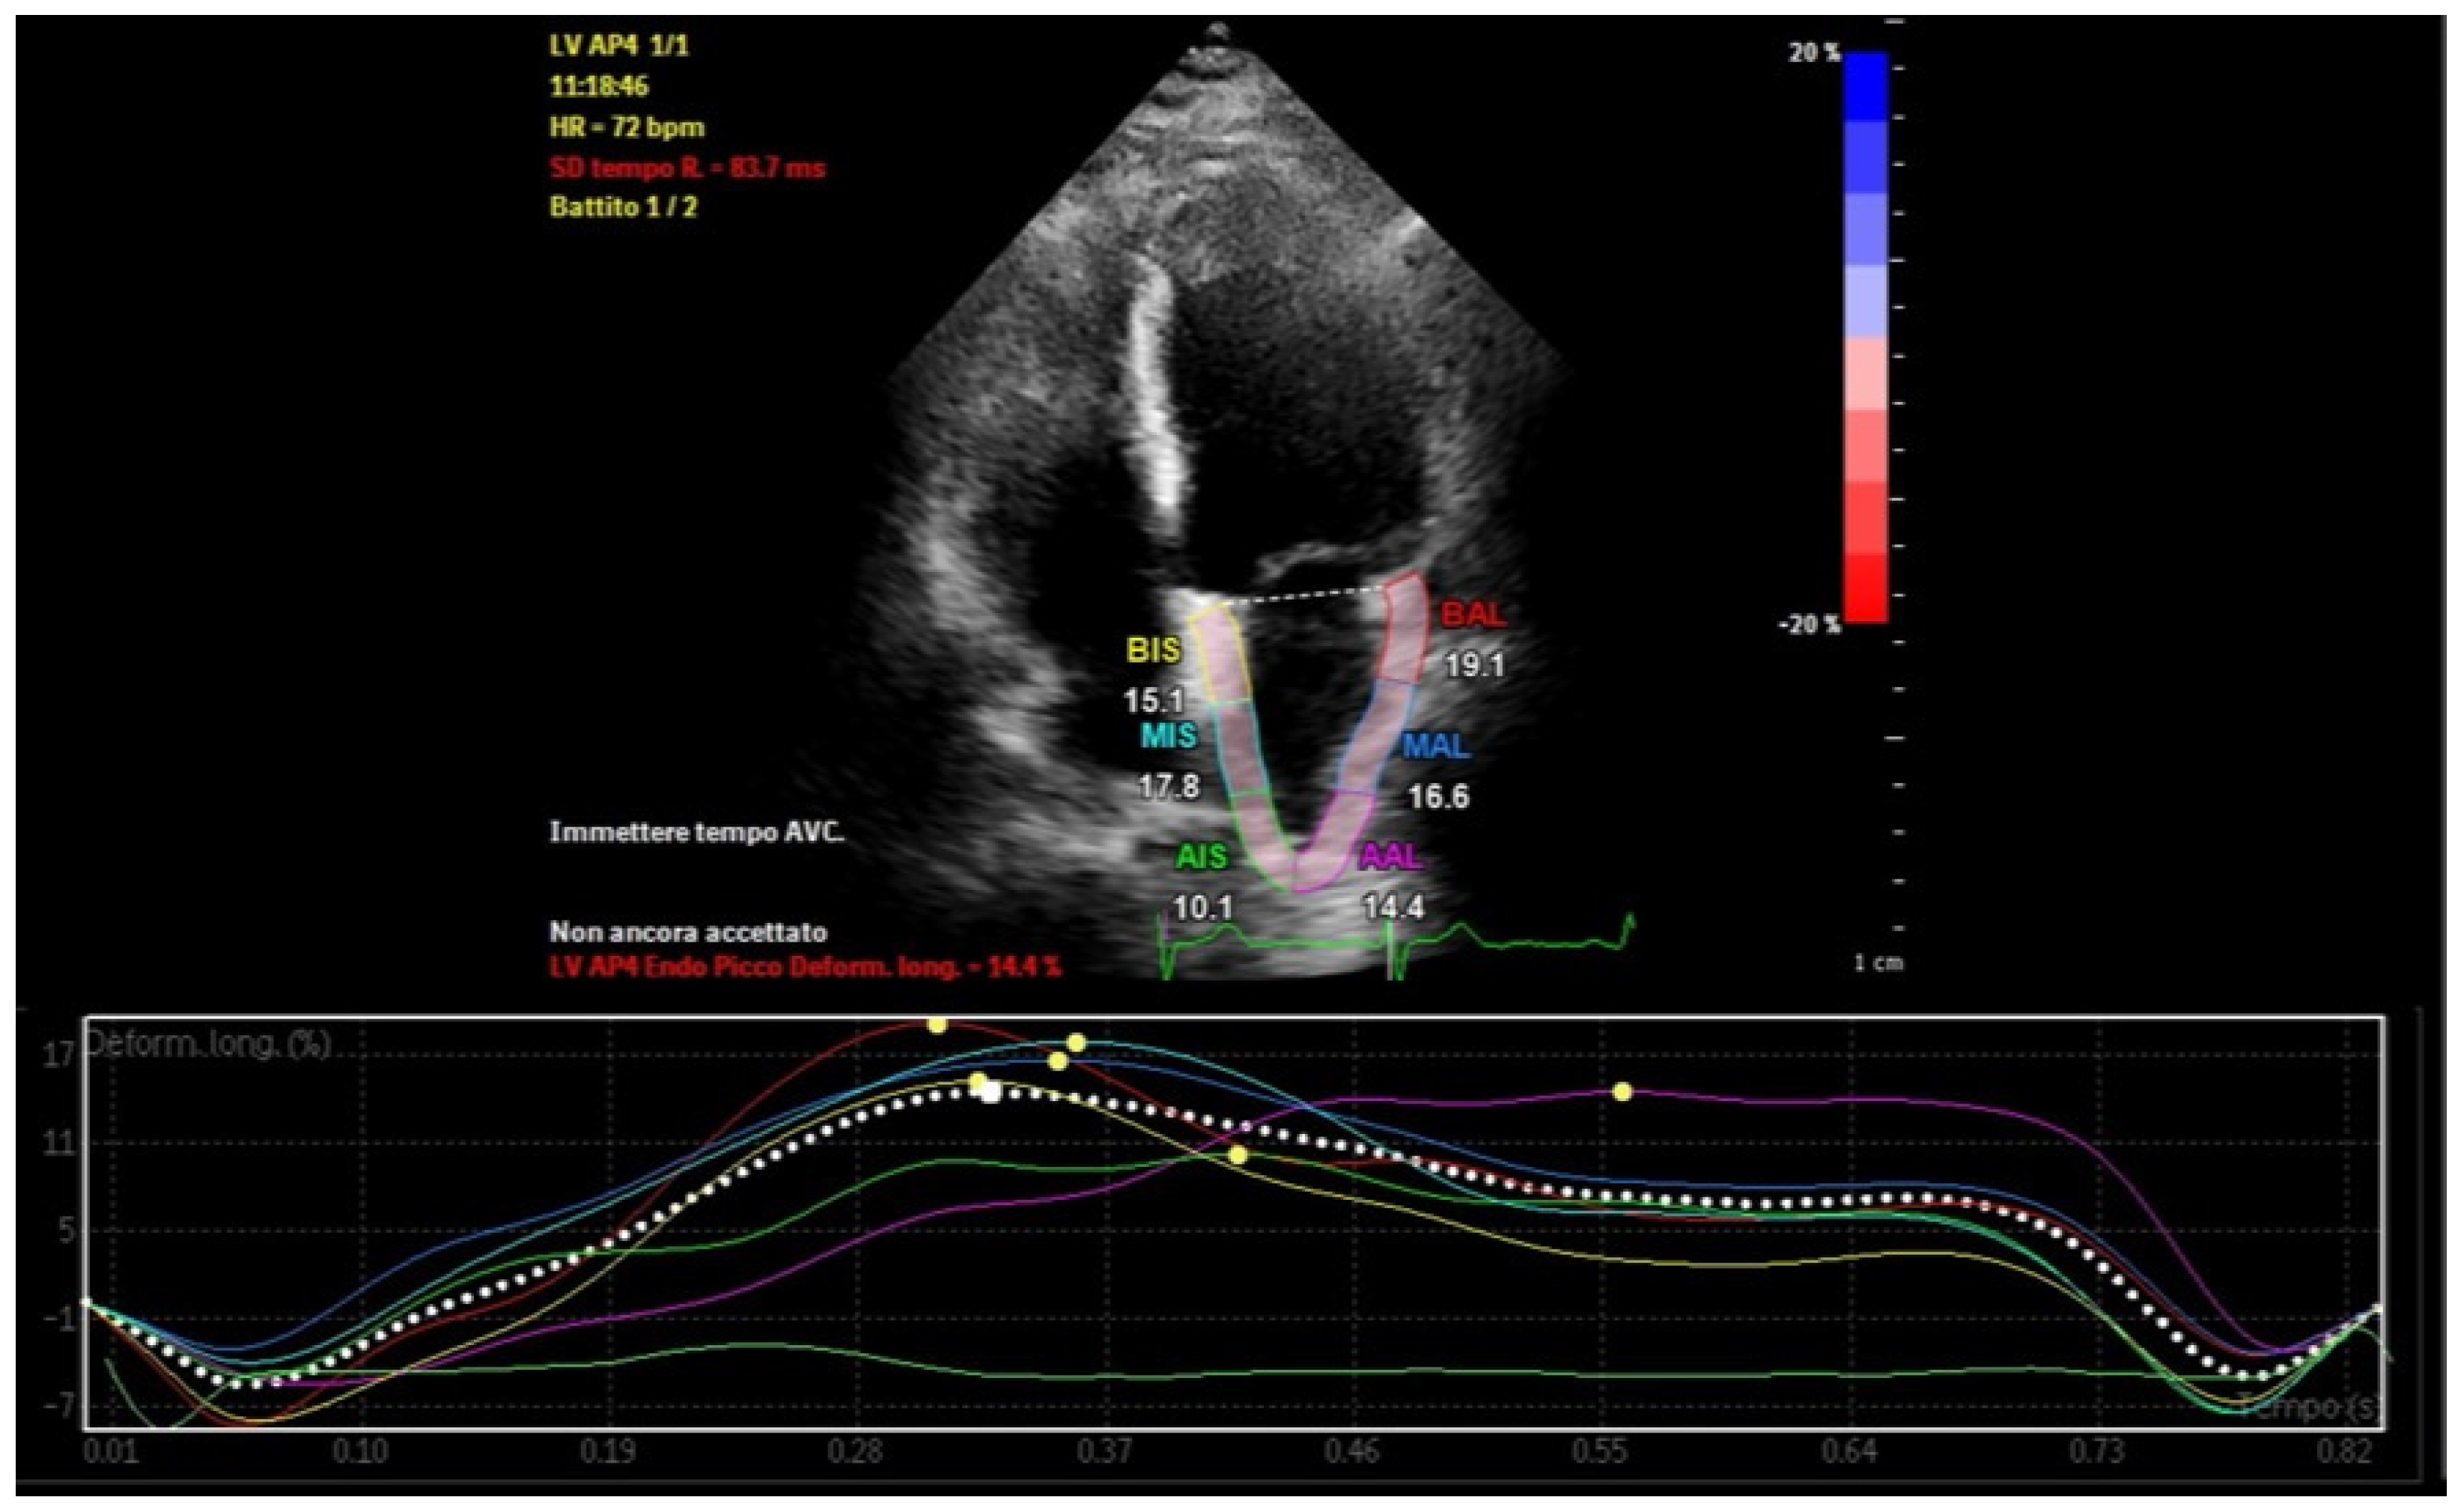

Atrial strain, assessed via speckle-tracking echocardiography, quantifies myocardial deformation and provides insights into atrial reservoir and contractile functions [23]. This technique allows early detection of subtle atrial dysfunction, even before structural abnormalities manifest [24]. Strain imaging also identifies and quantifies atrial dyssynchrony, which reflects temporal discrepancies in atrial deformation during the cardiac cycle (Figure 3) [25,26].

Figure 3.

Left atrial strain showing dyssynchrony in a patient with recurrent episodes of paroxysmal atrial fibrillation and abundant left atrial epicardial adipose tissue.

In healthy subjects, typical values for left atrial reservoir strain range from 35 to 45%, conduit strain from 18 to 25%, and contractile strain from 10 to 15% [45]. In contrast, patients with increased LA-EAT often exhibit markedly reduced values (Table 2): reservoir strain below 25%, conduit strain reduced to 12–18%, and contractile strain falling below 8% [46]. These reductions reflect the adverse mechanical and inflammatory effects of LA-EAT on atrial function.

Regional dyssynchrony in strain patterns is a prominent feature in these patients, characterized by variability in time to peak strain (TTP) across atrial segments (Figure 6). This variability indicates asynchronous contraction, with the posterior and inferior walls of the left atrium—regions adjacent to EAT deposits—frequently showing the most delayed TTP. Strain curves in these segments often exhibit nonuniformity, with delayed or flattened peaks compared to unaffected regions. Segments nearest to large EAT deposits demonstrate the greatest dyssynchrony, underscoring the localized impact of EAT on atrial mechanics [55].

Figure 6.

Left atrial strain in a patient with abundant left atrial epicardial adipose tissue. Time−to−peak variability and reduced peak atrial longitudinal strain are recorded.

The global dyssynchrony index, defined as the difference between maximum and minimum TTP across all atrial segments, quantifies this dyssynchrony. In patients with increased EAT, the index is significantly elevated, often exceeding 20%, compared to less than 10% in healthy individuals [56,57]. This disparity highlights EAT’s role in disrupting atrial synchrony.